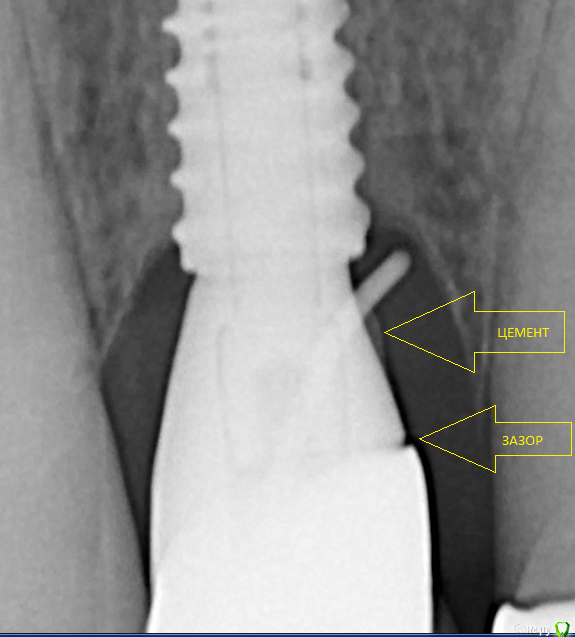

___49___ Опубликовано 18 декабря, 2018 Поделиться Опубликовано 18 декабря, 2018 (изменено) Винт в позиции 11, имплантация около года назад, протезирование примерно полгода как.На контрольном осмотре выявлен свищ в проекции 2-3 витка, при зондировании витки определяются, дальше к верхушке - кость. При внутриротовом снимке гутаперча остается на уровне платформы. Жалоб абсолютно никаких.Вопросы, два извечно русских: что делать и кто виноват? МГ.JPGВас это не смущает ? Изменено 18 декабря, 2018 пользователем ___49___ 6 Ссылка на комментарий

bullbull Опубликовано 18 декабря, 2018 Автор Поделиться Опубликовано 18 декабря, 2018 Спасибо. Я думал цемент более контрастный. Зазор мог стать причиной?Задам пару вопросов своим ортопедам.Делать кюретаж с откидыванием? Косточку стоит сыпать? Ссылка на комментарий

Борис80 Опубликовано 18 декабря, 2018 Поделиться Опубликовано 18 декабря, 2018 (изменено) Зазор мог стать причиной?Задам пару вопросов своим ортопедам. Скорее цемент почистить, убрать цемент Изменено 18 декабря, 2018 пользователем Борис80 2 Ссылка на комментарий

___49___ Опубликовано 18 декабря, 2018 Поделиться Опубликовано 18 декабря, 2018 Спасибо. Я думал цемент более контрастный. Зазор мог стать причиной?Задам пару вопросов своим ортопедам.Делать кюретаж с откидыванием? Косточку стоит сыпать?Вот поэтому я за винт там где это возможно . Как только вы откинете лоскут от резьбы - считай переимплантит запущен - дело времени, если все же придется откидывать лоскут(так как другим путем почистить не удастся ) - расщепляйте мягкие ткани так , чтобы резьба не открылась . Ссылка на комментарий